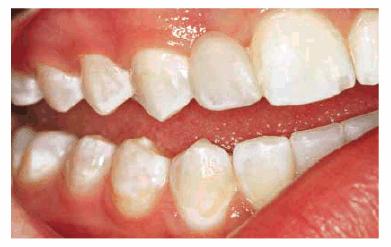

Some examples of these different discolorations can be seen in Figures 16-2A

and B 16-8A and B 16-11A and B 16-12A and B, and ,. Additionally, the discoloration

can either be of a generalized nature or specific to one tooth or one location

on a tooth (Table 16-2).